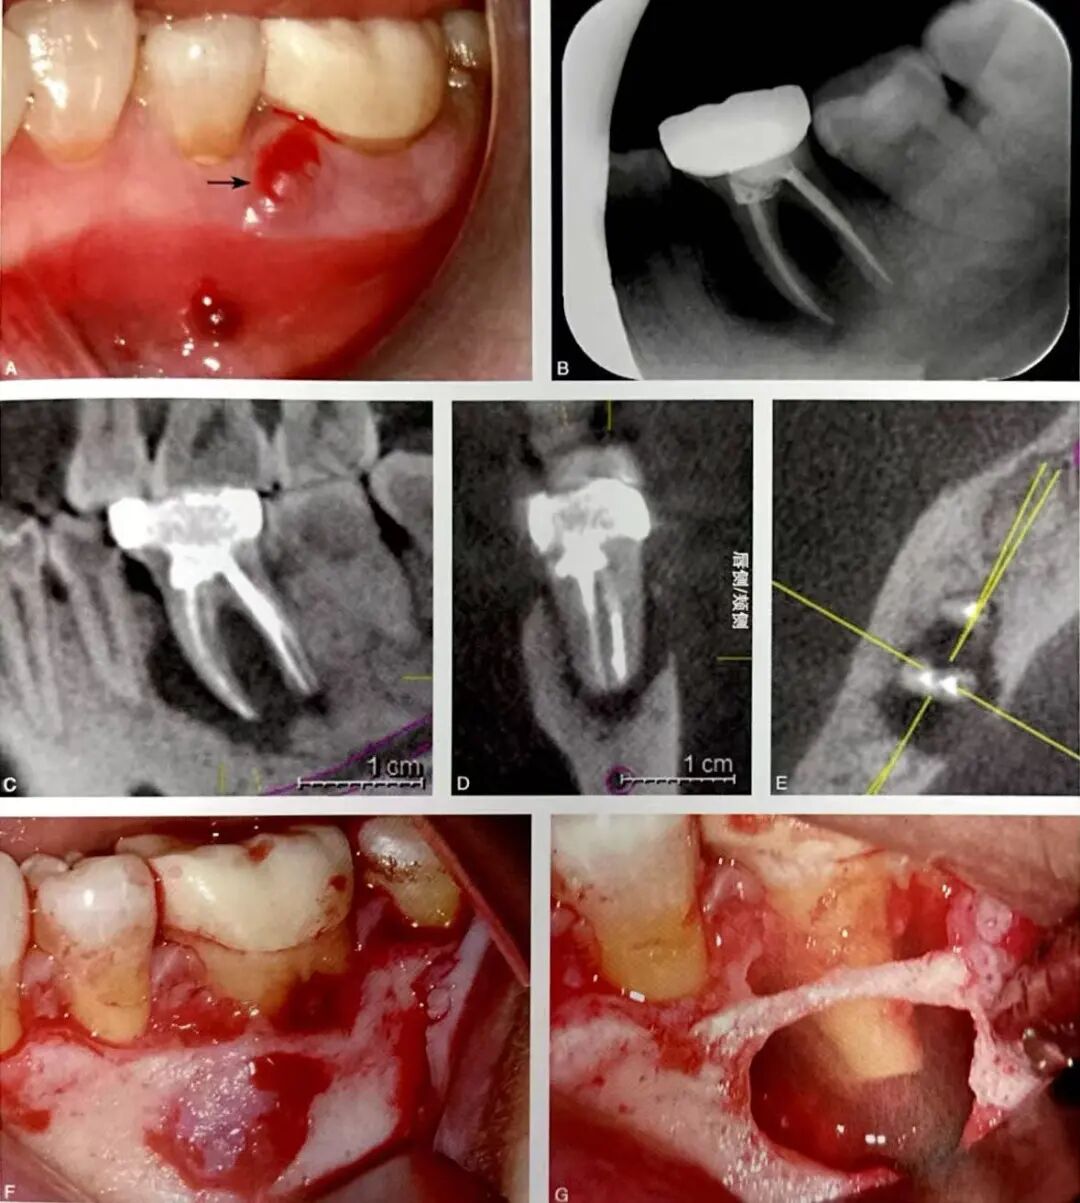

图1 右下颌第一磨牙近中根根裂。A为口内像示右下颌第一磨牙颊侧根尖区窦道;B为根尖片,示近中根根管充填良好,根周透射影;C为CBCT失状位;D为CBCT冠状位;E为CBCT水平位,示近中根根尖以及根周骨质破坏、颊侧骨板缺损;F为右下颌第一磨牙行显微根尖外科手术,切开翻瓣牵拉,见近中根颊侧骨板缺损;G为染色探查,近中根见贯穿牙根全长的颊舌向根裂线